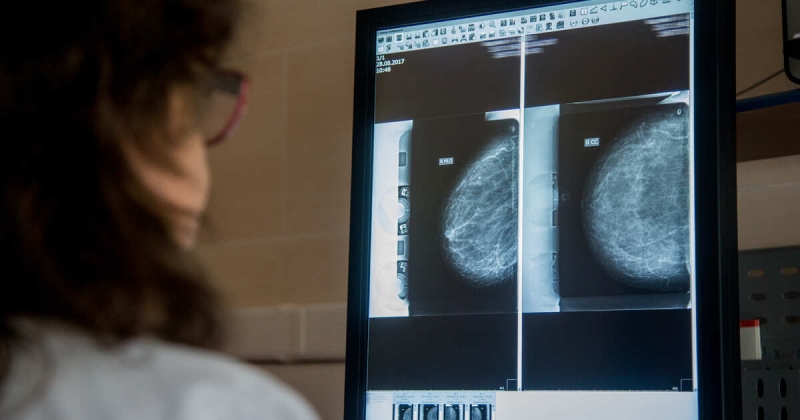

Женщины, которые пропускают первое обследование на рак груди, имеют на 40% более высокий риск смерти от этого заболевания. Об этом сообщает The Guardian.

Ученые Каролинского института в Швеции проанализировали данные около полумиллиона женщин, которые получили первое приглашение на маммографию в период с 1991 по 2020 год. В ходе исследования почти треть (32%) женщин не пришли на первое обследование. У тех, кто пропустил первую встречу, был значительно более высокий риск смерти от рака груди – 9,9 случая на тысячу женщин за 25 лет по сравнению с семью случаями среди тех, кто прошел проверку. Кроме того, такие женщины реже посещали последующие обследования и чаще сталкивались с диагнозами на более поздних стадиях рака.

Участие в первом обследовании важно не только для краткосрочной диагностики, но и для «долгосрочного инвестирования в здоровье и выживание», отметили специалисты. Они добавили, что даже простое посещение обследования и получение информации о том, как снизить риски рака и на что обращать внимание, имеет большое значение для долгосрочного здоровья.